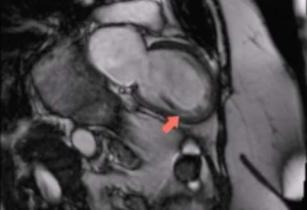

Diagnosing myocarditis with the help of CMR 26th Sep 2017 - Andrew R. Houghton, MD Learn how cardiac MRI can help you make a diagnosis of myocarditis. Taken from our CME accredited CMR Essentials ...